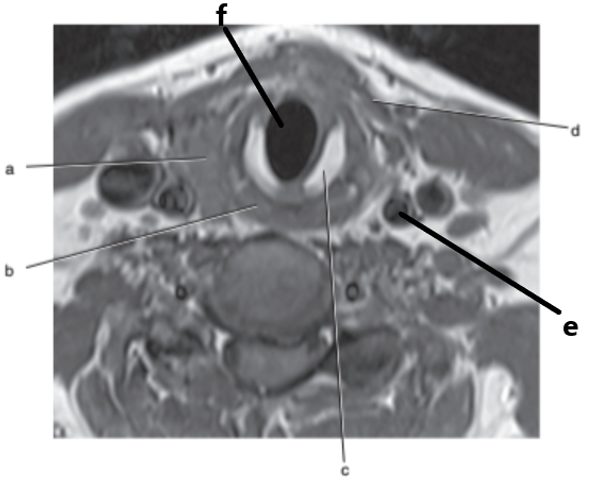

Trachea

Thyroid gland

Larynx

Spinal cord

Vertebral artery

What is letter b ?

Esophagus

Cricoid cartilage